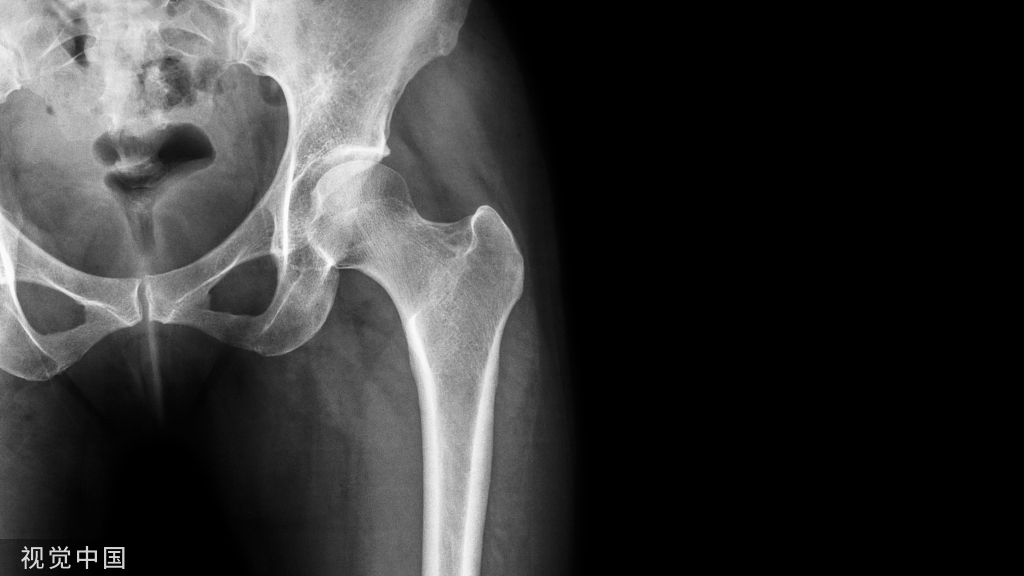

尚未形成新月征的股骨头坏死

已经形成新月征的股骨头则是这样: